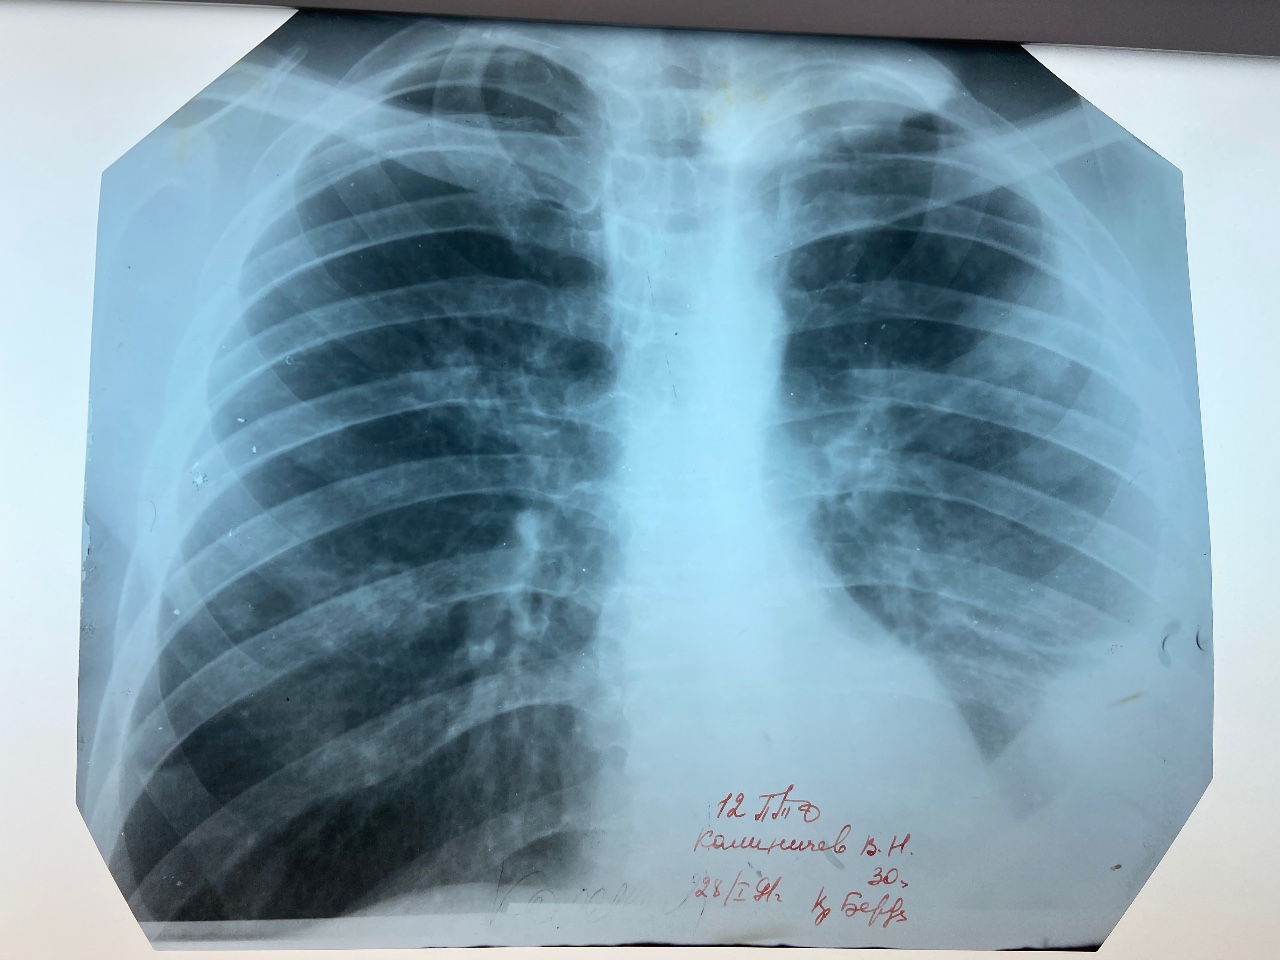

Что такое малоконтрастная рентгенограмма органов грудной клетки